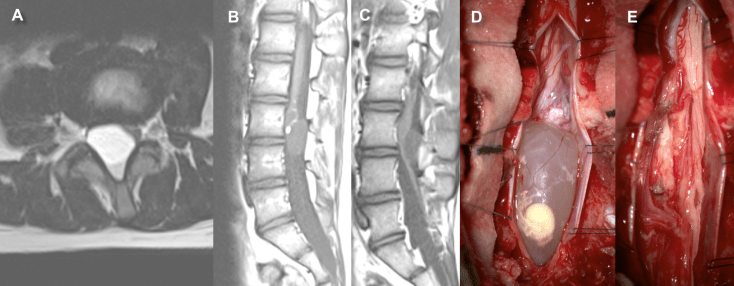

le kyste dermoïde

il peut être :

- dysraphique, reliquat d’une fistule excisée incomplètement et qui continue à évoluer même à l’âge adulte

- ou non dysraphique, correspondant à une inclusion de tissu épidermique ou dermique en intradural sans spina bifida ; à noter les anecdotiques dermoïdes d’inclusion secondaires à une ponction lombaire